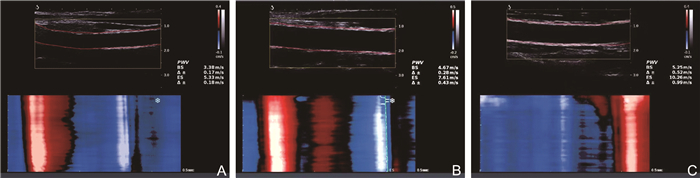

极速脉搏波技术在系统性红斑狼疮亚临床动脉粥样硬化中的评估价值及其临床相关因素研究

王星, 陆芳, 石彦, 李阳, 谢长好

2025, 23(7): 1192-1195. doi: 10.16766/j.cnki.issn.1674-4152.004095

323 2

摘要:

目的  应用极速脉搏波技术评估不同活动度系统性红斑狼疮(SLE)患者的血管弹性并探究其相关危险因素。  方法  选取2020年10月—2024年4月就诊于蚌埠医科大学第一附属医院的116例SLE患者,根据SLE疾病活动性指数2000分为轻度活动组(57例)和中重度活动组(59例),纳入45名健康成年人作为对照组。测量各组的颈动脉内中膜厚度(IMT)、收缩期起始时的脉搏波传导速度(PWV-BS)及收缩期末的脉搏波传导速度(PWV-ES),比较3组颈动脉参数及临床资料,分析脉搏波传导速度(PWV)与各指标之间的相关性。  结果  3组间PWV-BS、PWV-ES比较,中重度活动组>轻度活动组>对照组(P<0.05)。PWV-BS与颈总动脉IMT(r=0.315, P < 0.001)、收缩压(r=0.190, P=0.041)、舒张压(r=0.191, P=0.040)呈正相关关系,PWV-ES与颈动脉分叉处IMT(r=0.274, P=0.003)、颈总动脉IMT(r=0.361, P < 0.001)、舒张压(r=0.252, P=0.006)呈正相关关系。  结论  SLE患者的颈动脉弹性减低明显早于健康者,极速脉搏波可定量评估SLE患者颈动脉弹性,且不受限于时期,这为临床早期动脉硬化评估提供了客观依据。